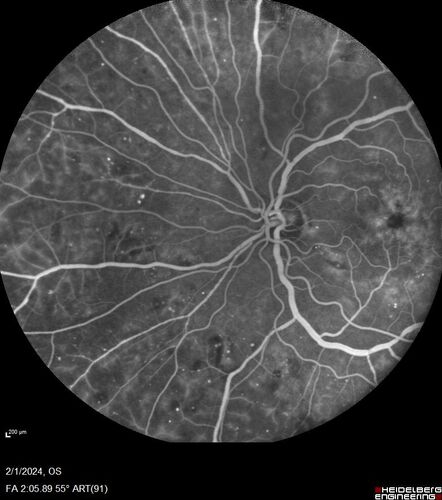

71 year old female with 3 months of vision loss and not feeling well.  She has been bruising on her legs.  Her vision was 20/100 in each eye with macular edema.  She was treated with Avastin and her CBC was checked.  She had a WBC of 267 thousand and was diagnosed with CML.

Chronic Myelogenous Leukemia and Diabetic Macular Edema